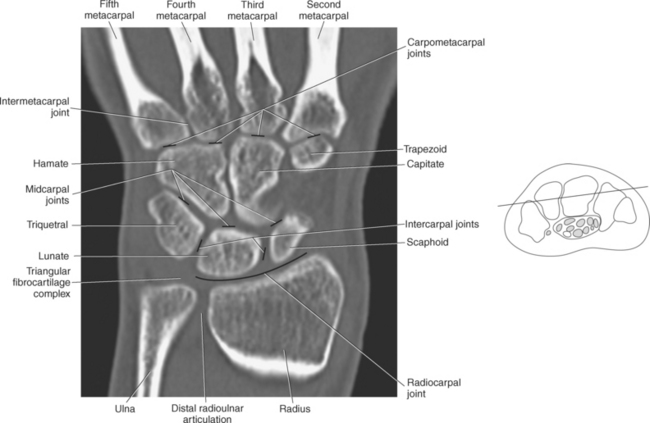

The bony anatomy of the wrist and hand consists of the distal radius and ulna, 8 carpal bones, 5 metacarpals, and 14 phalanges (Figure 9.101). Both the distal radius and ulna have a conical styloid process that acts as an attachment site for ligaments. The radial styloid process is located on the lateral surface of the radius, whereas the ulnar styloid process is located on the posteromedial side of the ulna. The carpal bones are arranged in proximal and distal rows. Located in the proximal row of carpal bones are the scaphoid (navicular), lunate (semilunar), triquetral (triquetrum), and pisiform bones. The pisiform is considered a sesamoid bone that is embedded in the tendon of the flexor carpi ulnaris. The distal row consists of the trapezium (greater multangular), trapezoid (lesser multangular), capitate (os magnum), and hamate (unciform) bones (Figures 9.102 through 9.114). The five metacarpals are small tubular bones with a proximal end (base), distal end (head), and shaft (body). The 14 phalanges that make up the fingers are short tubular bones. Like the metacarpals, each phalanx consists of a proximal (base), middle (body or diaphysis), and distal (head) portion. Each digit consists of 3 phalanges (proximal, middle, and distal), except for the thumb (first digit), which has only 2 phalanges (proximal and distal). The articulation of the phalanges of the second through fifth digits creates three interphalangeal joints: the metacarpophalangeal (MCP) joints classified as condyloid joints, proximal interphalangeal (PIP), and distal interphalangeal (DIP). The proximal and distal interphalangeal joints are classified as hinge joints (Figure 9.101). The first digit, which consists of 2 phalanges, has just two joints: the MCP joint, classified as a saddle joint, and an interphalangeal joint, classified as a hinge joint (Figure 9.101).

The joints of the wrist and hand are quite complex and consist of the following: distal radioulnar articulation, radiocarpal articulation (proximal joint of hand), midcarpal articulation (distal joint of hand), intercarpal articulations (articulations between proximal and distal carpals), carpometacarpal articulations (between carpals and metacarpals), the intermetacarpal articulations (between bases of metacarpals two through five) and the interphalangeal joints (between phalanges of each digit) (Figures 9.111 and 9.115). The distal radioulnar articulation, also called the distal radioulnar joint (DRUJ), is created when the ulnar notch of the radius moves around the articular circumference of the ulna, providing the movements of supination and pronation. The main stabilizing element of the DRUJ is an articular disk called the triangular fibrocartilage complex (TFCC). The TFCC is a fan-shaped band of fibrous tissue that originates on the medial surface of the distal radius and traverses horizontally to insert on the ulnar styloid process (Figures 9.115 and 9.116). It rotates against the distal surface of the ulnar head during pronation and supination and separates the ulna from the carpal bones. The proximal surface of the radiocarpal articulation is formed by the articular carpal surface of the radius and the TFCC, whereas the distal surface is formed by the articular surfaces of the scaphoid, lunate, and triquetrum and the interosseous ligaments connecting them (Figures 9.111 through 9.115). The midcarpal joint is formed by the articulations between the proximal and distal carpal rows (Figures 9.110 and 9.115). The articulation between the carpals within each row creates the intercarpal joints (Figures 9.111 and 9.115). The carpometacarpal joints are formed by the articulations between the carpus and the five metacarpals (Figure 9.111 and 9.115). The carpometacarpal joint of the thumb is an independent joint formed by the articular surfaces of the trapezium and first metacarpal, creating a pure saddle joint. The carpometacarpal articulations of the two to five digits are amphiarthrotic joints with little mobility (Figures 9.105 and 9.115). The intermetacarpal articulation exists between the base of the metacarpals and is joined by the palmar and dorsal metacarpal ligaments (Figure 9.115).

Figure 9.116 Coronal, T1-weighted MR scan of wrist with triangular fibrocartilage complex.

Key: t, Triquetrum; TFCC, triangular fibrocartilage complex; u, ulna; r, radius; s, scaphoid; l, lunate; H, hamate; C, capitate; Td, trapezoid; Tm, trapezium; P, pisiform; L, lunate; S, scaphoid; LT, Lister’s tubercle.

Numerous ligaments provide additional stability to the wrist. The extrinsic ligaments reinforce the joint cavity surrounding the carpal region and include palmar and dorsal radial carpal ligaments, the radial and ulnar collateral ligaments, and the TFCC (Figures 9.115 through 9.117). The many articulations between the carpal bones are supported by the intercarpal ligaments or intrinsic ligaments that connect the carpal bones to each other (Figure 9.115). The configuration of the intrinsic ligaments, metacarpal ligaments, and triangular fibrocartilage complex creates five different joint compartments that can be demonstrated at arthrography: (1) compartment of the first carpometacarpal articulation, (2) common carpometacarpal compartment, (3) mediocarpal compartment, (4) intermetacarpal compartment, and (5) radiocarpal compartment (Figure 9.115). The carpal tunnel is created by the concave arrangement of the carpal bones (Figure 9.103). A thick ligamentous band called the flexor retinaculum (transverse carpal ligament) stretches across the carpal tunnel to create an enclosure for the passage of tendons and the median nerve (Figures 9.118 through 9.120). The flexor retinaculum inserts medially on the pisiform and hook of the hamate and spans the wrist to insert laterally on the scaphoid and trapezium. In addition to the carpal tunnel, another tunnel called Guyon’s canal is formed where the ulnar extension of the flexor retinaculum continues over the pisiform and hamate. This creates a potential site for compression of the ulnar nerve (Figures 9.118, top, and 9.119). The extensor retinaculum (dorsal carpal ligament), located dorsally, is much thinner. It attaches medially to the ulnar styloid process, triquetrum, and pisiform and laterally to the lateral margin of the radius (Figure 9.120, left). Along its course it forms six fibroosseous tunnels for the passage of the synovial sheaths containing the extensor tendons (Figure 9.118, bottom).